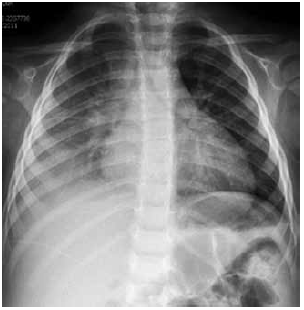

Criança de 1 a 5 m dá entrada no pronto atendimento com história de febre há 5 dias e cansaço hoje. Ao exame físico apresenta: regular estado geral, descorada+, hidratada, acianótica, anictérica, sonolenta, taquidispneia moderada (batimento de asa de nariz e retração intercostal), FR-50, FC-130, PA 80 x 50, Sat 88% em ar ambiente, pulsos firmes (central e periférico) e tempo de enchimento capilar – 2 segundos. Ausculta pulmonar: murmúrio vesicular presente bilateralmente, bastante diminuído em base direita, e com estertoração creptante à direita. A criança foi colocada na sala de emergência, monitorizada, ofertado oxigênio em máscara com reservatório, sem reinalação, 15 litros de oxigênio/min com melhora da saturação – 100%. Obtido acesso venoso periférico, e coletados exames: hemograma, PCR, hemocultura e solicitado radiografia tórax no leito.

Com relação à conduta inicial, hipótese diagnóstica e conduta a ser tomada posteriormente, assinale alternativa correta.